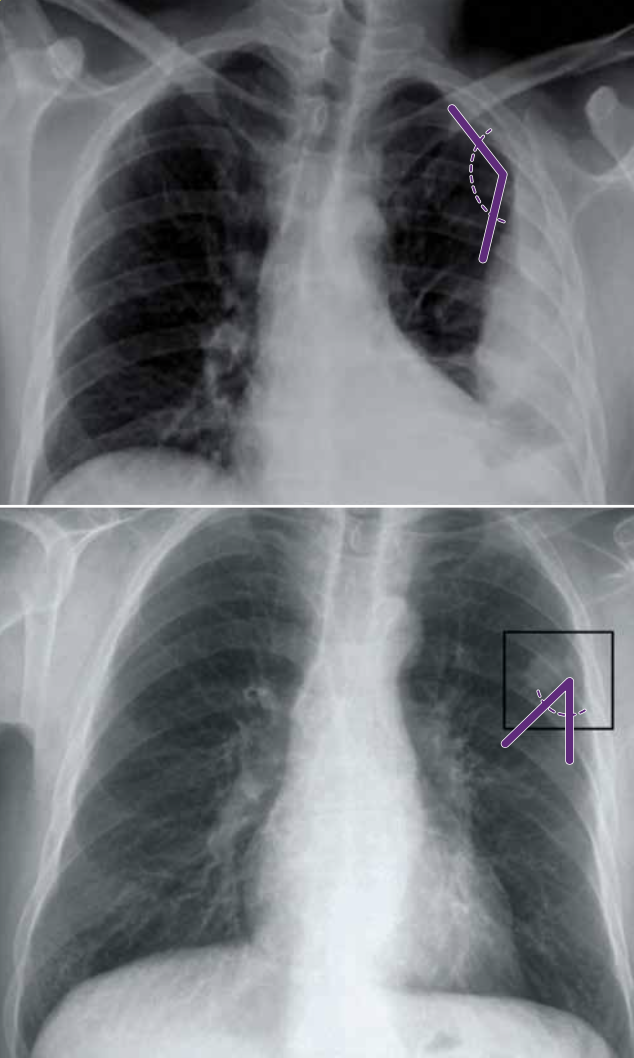

Consolidación con pérdida de volumen y lesiones cavitadas en lóbulo superior derecho. Además, se observa consolidación periférica basal derecha.

Ante una lesión cavitada debes:

• Valorar el grosor de la pared. Una pared gruesa e irregular sugiere neoplasia, mientras que los neumatoceles o quistes broncogénicos tienen paredes finas y más regulares.

• Valorar el contenido. Aparte del nivel hidroaéreo, un hallazgo típico aunque raro es el del aspergiloma, en forma de bola blanca en el interior.